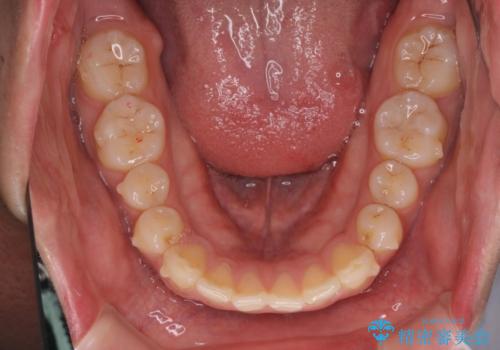

前歯が気になる。インビザラインライト

- 前歯が気になるとの事で来院。

矯正を希望されたが費用と時間を抑えたいとの事でインビザラインライトで矯正を行いました。(奥歯の位置関係はほぼ変えない)

前歯が綺麗に並び大変満足して頂けました。